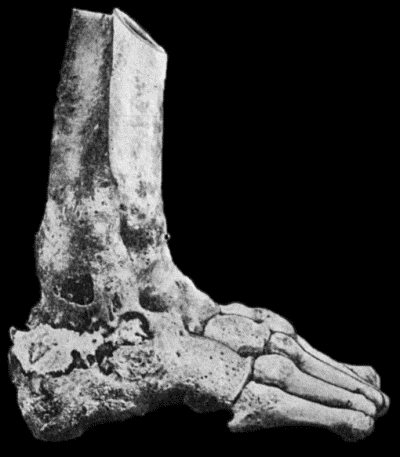

35.Tuberculous Sinus injected through its opening in the Forearm with Bismuth Paste 144

127.Advanced Tuberculous Disease in Region of Ankle 459